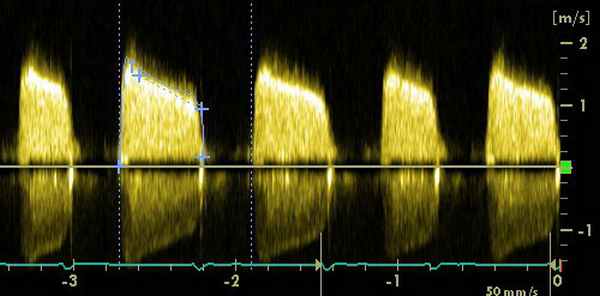

Самым надежным показателем тяжести стеноза МК является площадь отверстия клапана, которая может быть рассчитана несколькими методами, кроме планиметрического. Всесторонняя оценка стеноза МК с помощью ДЭхоКГ включает:

1) определение пиковой митральной диастолической скорости с помощью НВ ДЭхоКГ;

2) средний ДР и TVI трансмитрального потока;

3) площадь отверстия МК, рассчитанную но РНТ: площадь отверстия МК = 220/РНТ;

4) площадь отверстия МК, определенная по уравнению непрерывности и методу PISA.

Метод РНТ — самый простой, но менее надежный для применения сразу после баллонной ангиопластики у больных с тяжелой АР или высоким давлением наполнения. Этот метод недооценивает тяжесть стеноза МК в этих ситуациях, поскольку укорачивается РНТ. Уравнение непрерывности нельзя использовать при выраженных АР или MP. На метод PISA не влияет наличие других пороков. ЭхоКГ-признаками тяжелого стеноза МК являются: